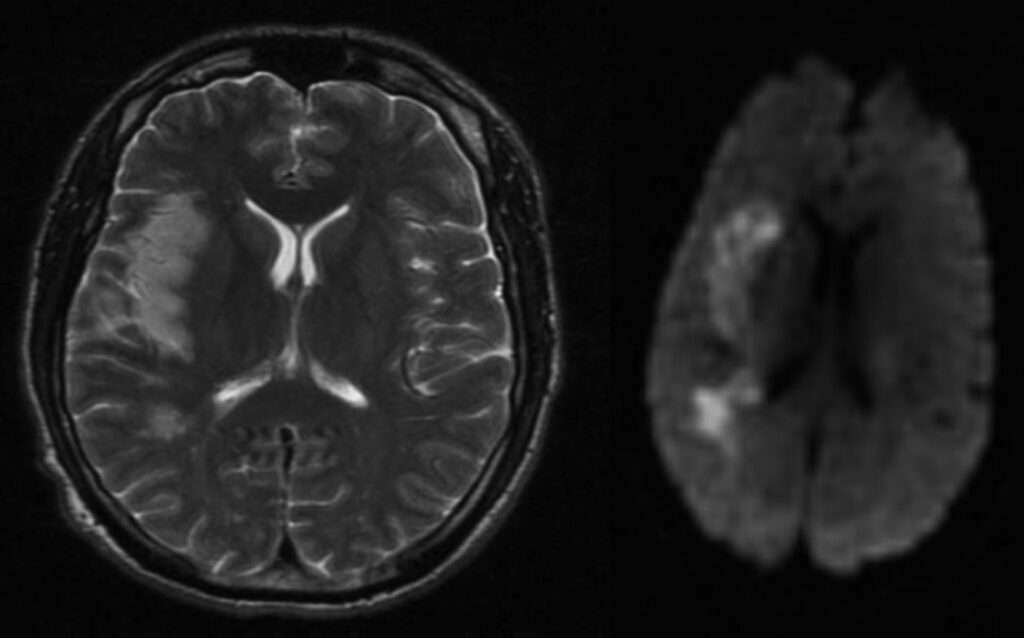

El accidente cerebrovascular es otra complicación temida de la meningitis tuberculosa. Se produce como resultado de una arteritis que afecta a los vasos del polígono de Willis, especialmente a las arterias perforantes que irrigan estructuras profundas del encéfalo, como los ganglios basales y el tálamo. La inflamación de las paredes vasculares conduce a estenosis, trombosis y, en consecuencia, a infartos isquémicos, cuyas secuelas pueden ser graves e irreversibles. Esta vasculopatía se conoce como «vasculitis de las arterias perforantes» y es una de las principales causas de déficit neurológico focal en estos pacientes.

Además, la obstrucción del flujo normal del líquido cefalorraquídeo constituye una complicación estructural crítica. El exudado denso y caseoso que se acumula en las cisternas basales puede bloquear la circulación del líquido cefalorraquídeo, particularmente a nivel de los ventrículos y de los acueductos, dando lugar a una hidrocefalia de tipo obstructivo. Esta condición se manifiesta clínicamente con signos de hipertensión intracraneal, como cefalea, vómitos y alteraciones del estado de conciencia, y puede evolucionar hacia un deterioro cognitivo progresivo si no se trata de manera oportuna, por ejemplo, mediante derivación ventricular.